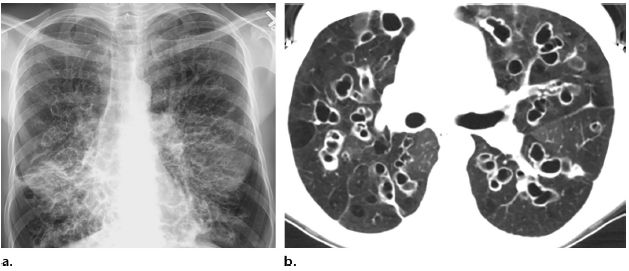

支氣管擴張的診斷主要依據(jù)患者的病史、癥狀和體征,以及輔助檢查如高分辨率CT掃描等,醫(yī)生會根據(jù)患者的具體情況進行綜合分析,以確定診斷。